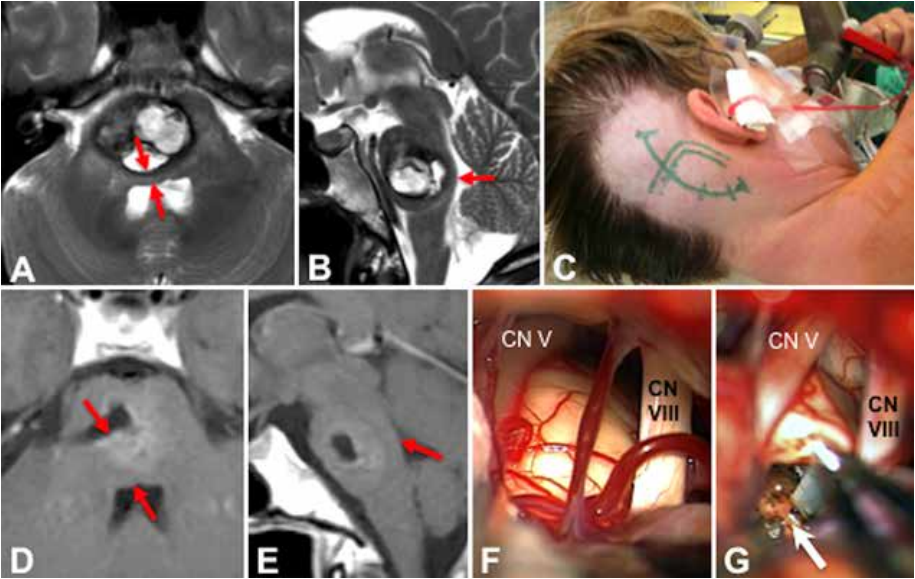

A和B:术前轴向(A)和矢状(B)T2加权图像显示大出血性C型(亚型CL)轴内桥脑海绵状血管瘤。脑桥的背侧结构受到严重压缩(红色箭头),表明仅在病变和菱形窝表面之间有薄薄的实质层。

C:患者保持左侧公园长椅位,主刀医生通过乙状窦脑桥后外侧入路进行开颅手术,同时暴露远端横窦。

D和E:术后对比增强轴向(D)和矢状(E)T1加权MR图像上记录了切除情况。减压后,切除腔背侧的脑桥实质已明显展开并恢复了明显的宽度(红色箭头)。

F和G:术中,在三叉神经(CN V)和耳蜗(CN VIII)神经;该区域被选为脑桥的入口点(G,白色箭头),这两个神经得到完整保留。患者术后病程平稳,无其他神经系统疾病。

45岁女性,大量急性出血,C型桥脑海绵状血管瘤,病变占据整个脑桥中央区域。患者术前瘫痪,卧床不起,意识障碍。左侧偏瘫和偏侧感觉减退,以及右侧面瘫、第六神经麻痹和严重吞咽困难。